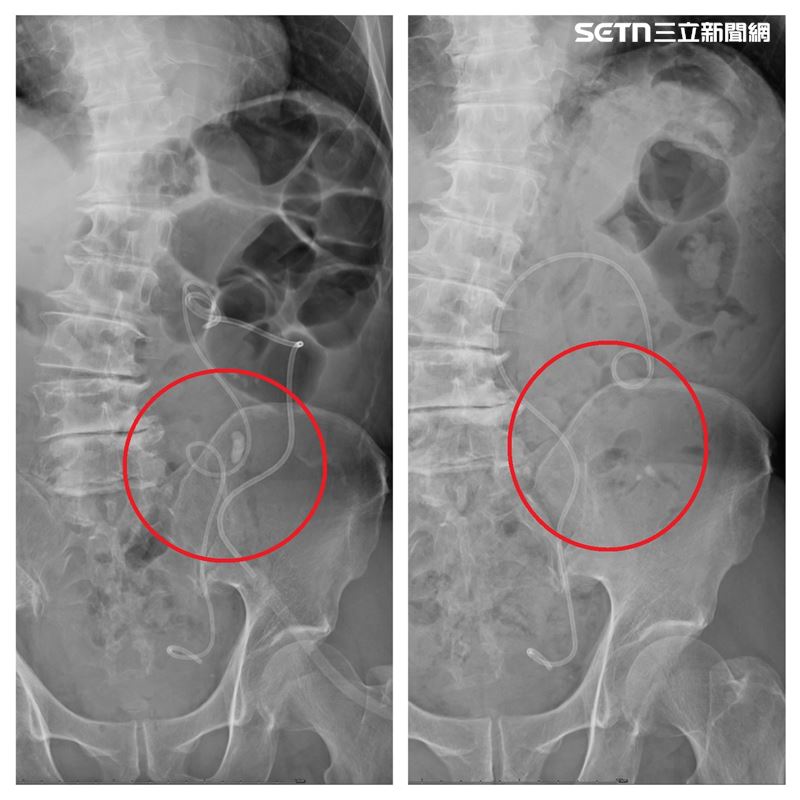

尿色像咖啡可不是小事!70歲陳姓男子為中部知名塑膠射出工廠老闆,長年忙於事業忽略健康,近日發現排尿困難、尿味又臭又濃、顏色深如咖啡,驚覺異常緊急就醫,衛生福利部豐原醫院泌尿科主任林德祺指出,經檢查發現,陳先生左側輸尿管被一顆約1.8公分的結石卡住,造成嚴重腎水腫與輸尿管彎曲,若再拖延恐引發腎功能受損甚至敗血症,所幸透過軟式輸尿管鏡結石碎除手術,順利清除結石、保住腎臟功能。

衛生福利部豐原醫院泌尿科主任林德祺表示,原本計畫採用傳統硬式輸尿管鏡取石,但由於患者輸尿管嚴重彎曲,如同雲霄飛車軌道,鏡體根本無法進入,醫療團隊迅速啟用最新一代「7.5Fr軟式輸尿管鏡」,細如筆身,靈巧自如,能靈活穿梭於曲折如迷宮的輸尿管中,隨著鏡頭抵達結石處,高能雷射瞬間擊碎石塊,搭配可彎可吸導管同步吸出碎屑,手術過程一氣呵成,最終成功解除阻塞,讓腎臟壓力釋放、尿路再現通暢。泌尿科主任林德祺表示,術後隔天陳先生即可下床行走,尿液恢復清澈,笑稱「現在只希望尿液永遠別再像咖啡!」,也展現豐原醫院醫療團隊高超技術與設備優勢。